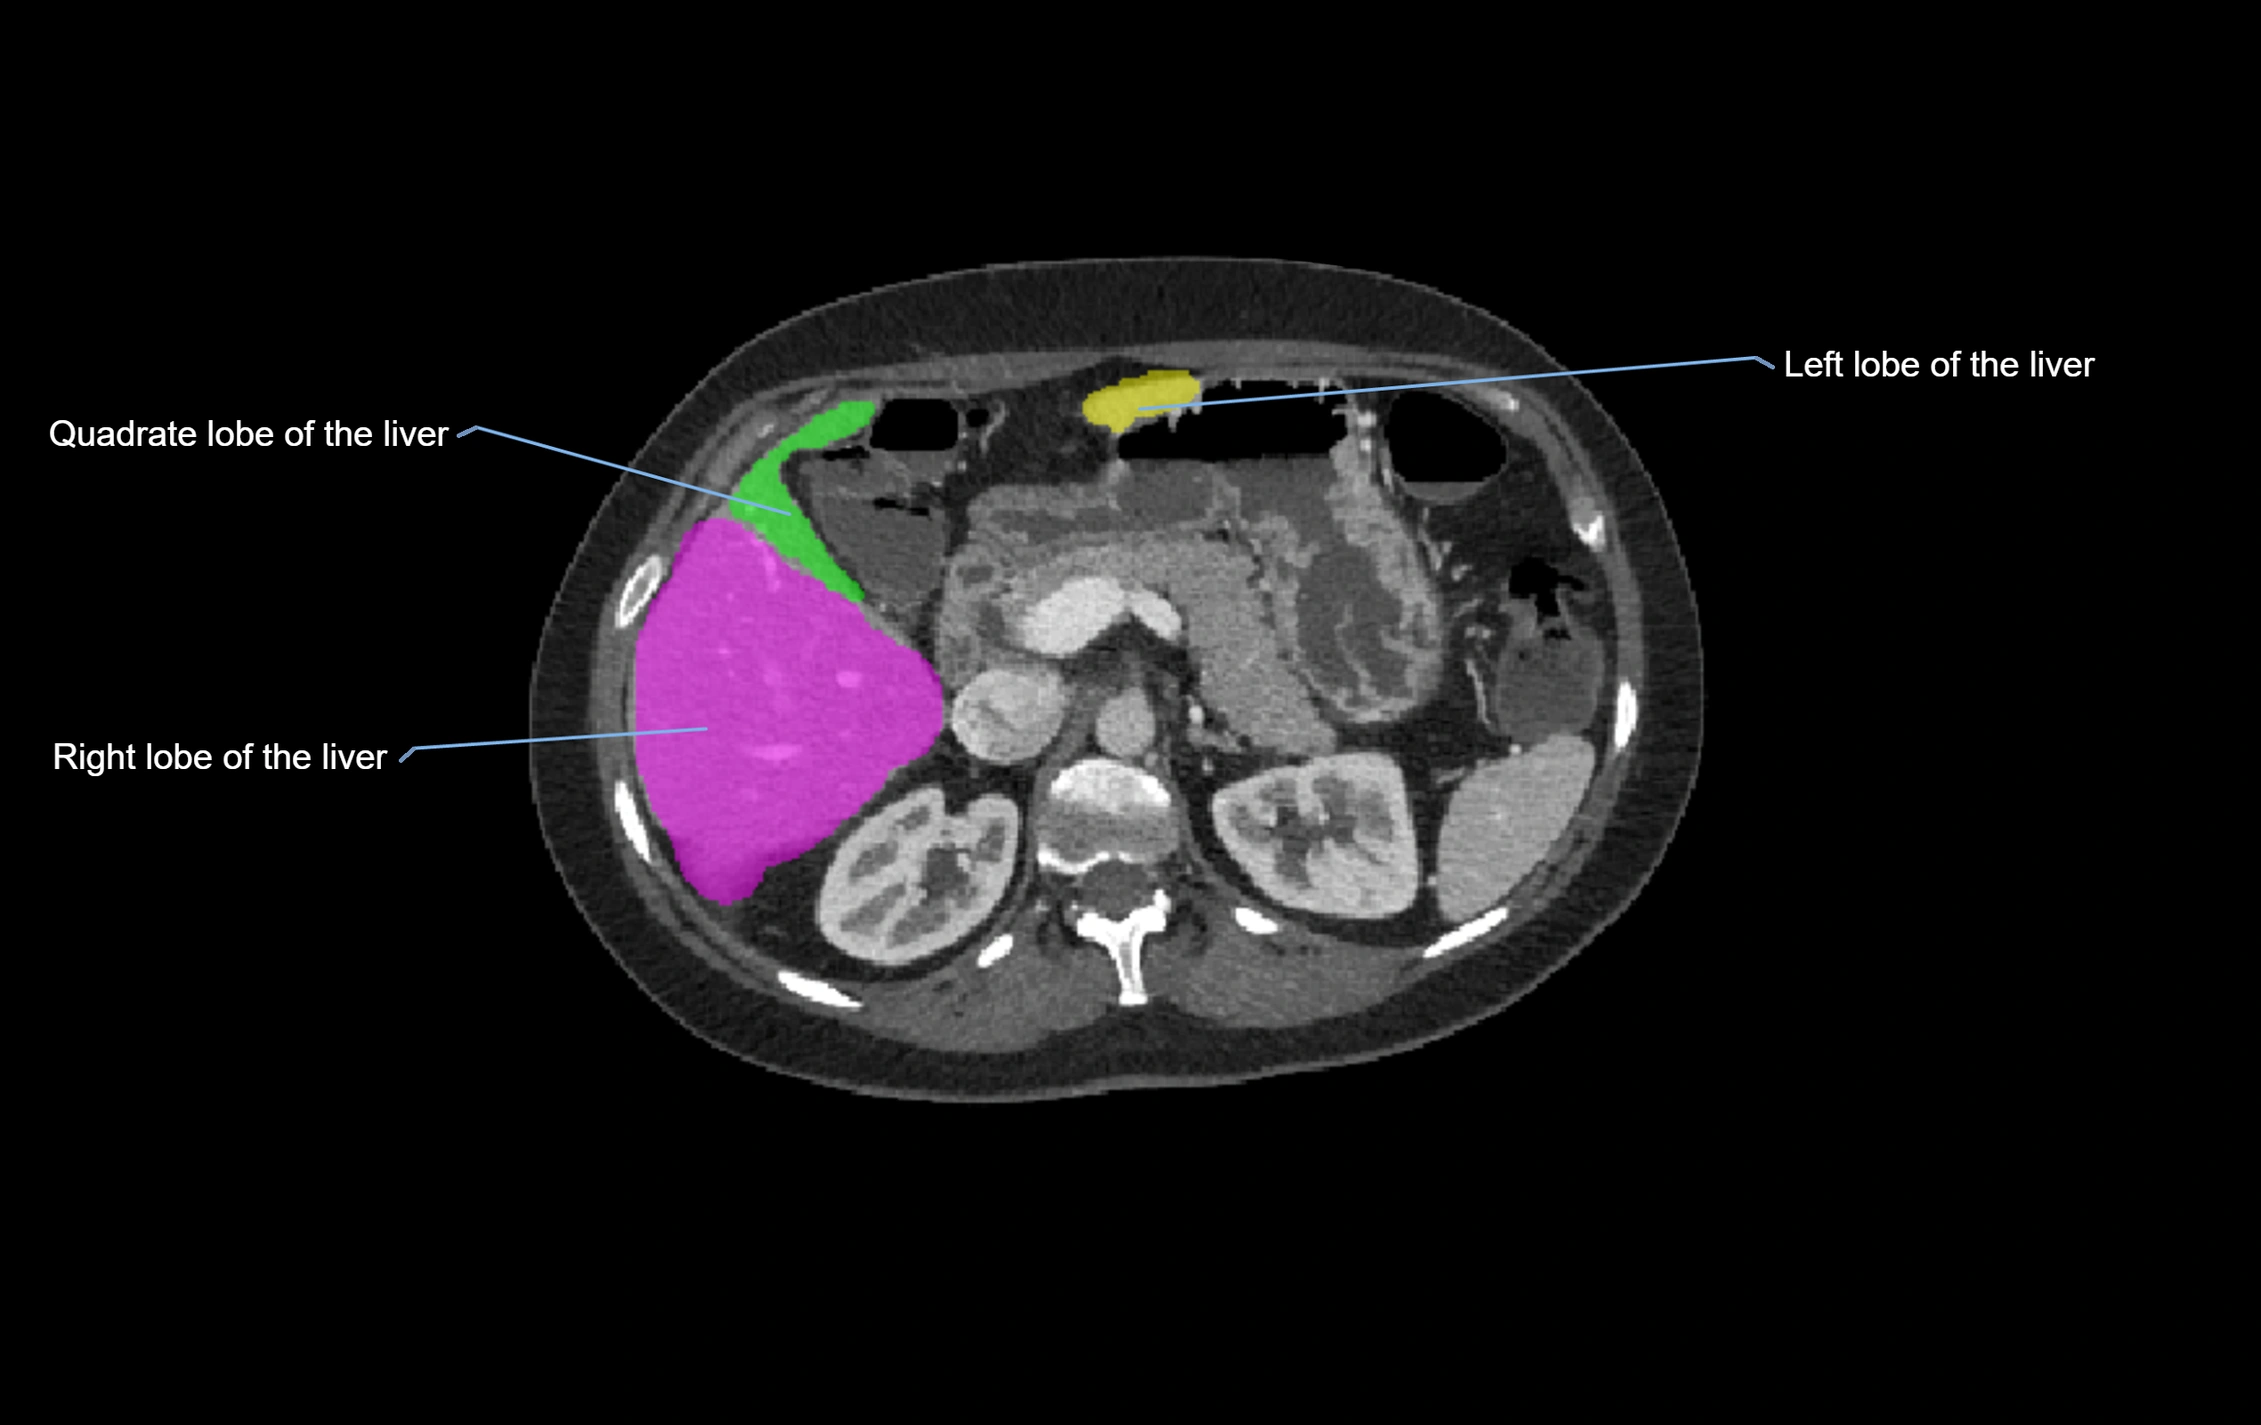

CT Image

image